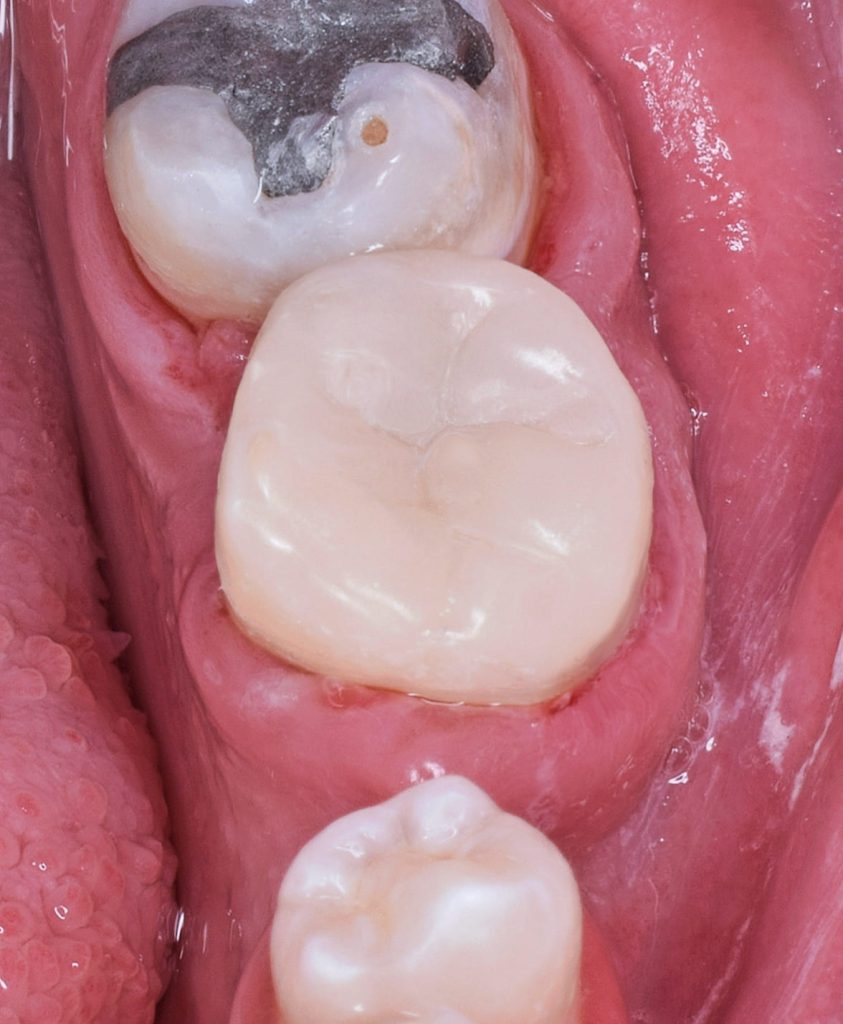

Gingivectomy - Gingival polyp removal

Direct view for isolation